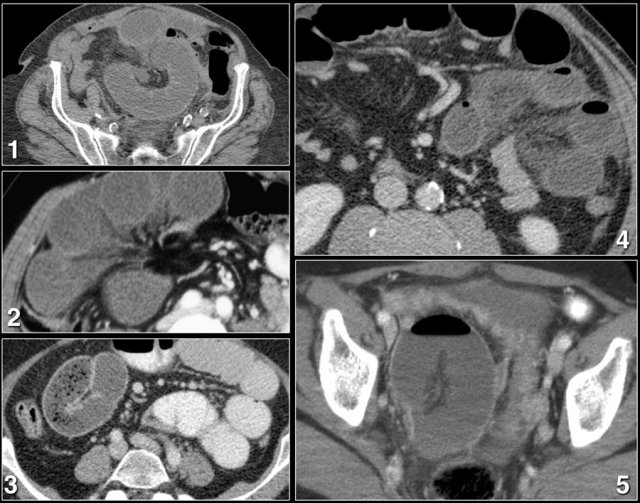

Two points of obstruction

Although an odd configuration of bowel loops and mesenteric edema in a patient with a small bowel obstruction are probably a good indication for surgery, finding two points of obstruction will give you 100% confidence in diagnosing a closed loop obstruction.

The two points of obstruction are always within 2 cm of each other so you don't have to look far, but they can be in any plane, so you need reconstructions.

The video shows you the images without comment first.

Try to find the closed loop with the two points of obstruction.

Then continue the video with commentary.

Need for reconstructions

In order to find the two stenoses you need reconstructions.

Some closed loops are obvious on axial images, but sometimes reconstructions in multiple planes are necessary.

Is there always dilatation of bowel?

Of course, the answer to this question is no.

The dilatation of the small bowel proximal to the closed loop and the dilatation within the closed loop depend on the amount of obstruction at the two stenoses and the time before the patient gets to CT and surgery.

In most cases both the proximal bowel and the closed loop are dilated, but sometimes there is only dilatation of the proximal bowel or only of the closed loop.

When the obstruction is very acute and there is no time delay, the bowel may not be dilated at all, which can make the diagnosis difficult.

This is a patient without prior surgery who presented at the ER with acute abdominal pain for two hours.

This patient has a closed loop obstruction.

Notice that there is no dilatation of the small bowel, both on CT and at surgery.

After cleavage of the adhesion the bowel was placed back into the abdomen and re-inspected after 10 minutes.

The 1.5 meter of ischemic bowel had regained a normal color.

This patient left the hospital the following day, in good condition.